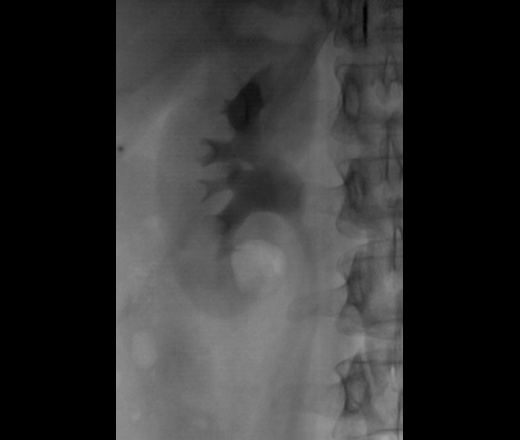

Классика жанра. Внутривенная урография.

Фрагменты рентгенограмм.

Неполная стриктура пиелоуретерального сегмента с престенотическим расширением лоханки с наличием "псоас-симптома".

Раз классика жанра, значит должно быть что-то известное. Но просто узнаваемого не вижу. Имеется субкомпенсированная стриктура лоханочно-мочеточникового сегмента правой почки с развитием гидрокаликоза и пиелоэктазии (гидронефрозом не назову, т.к. паренхима не истончена), да, с "+" псоас симптомом. Однако, постстенотическое расширение правого мочеточника, плавно теряющее контраст дистально, обусловлено гигантской миомой матки, сдавливающей мочеточник извне. Странно, как слева того же не произошло.